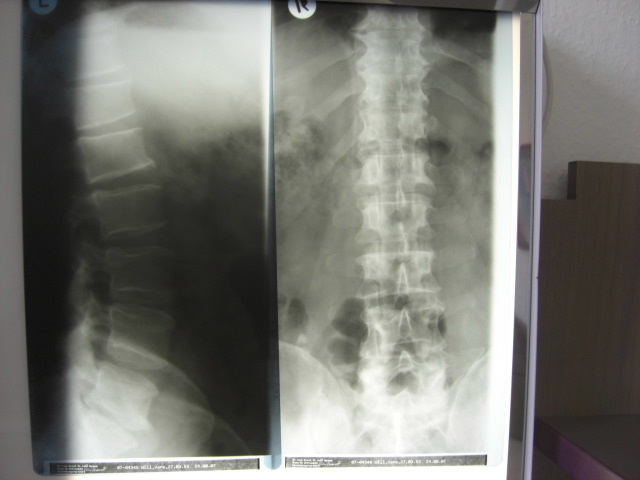

Zehn Jahre Rückenschmerzen wurden nach einer OP in Fürth beendet. Vorher hatte ich viel probiert. Ich kenne viele Radiologische Einrichtungen in Mainfranken. Ich habs mit Pferdesalbe versucht und ich war beim Osteopraktiker in Nürnberg und habe es mit Spritzen bei verschiedenen Orthopäden versucht. Nichts hat wirklich geholfen. Bis ich Dr.Schmidt in Fürth kennenlernen durfte. Er hat mit einem Blick auf das Röntgenbild erkannt was die Urache meines Schmerzes war. Gefahr erkannt, Gefahr gebannt. Ein schmerzhafter Lebensabschitt ging zu Ende.